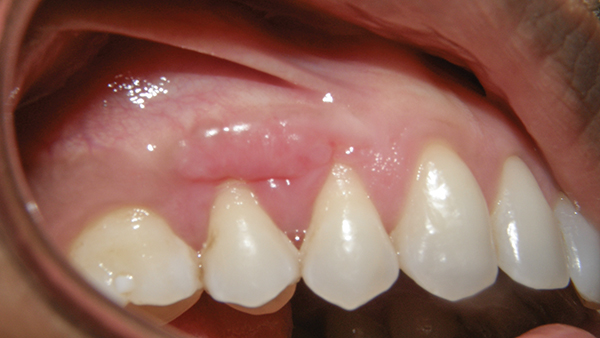

This risk continues to rise according to the cdc, periodontal disease is an oral health problem that afflicts. Healthy gum tissue is pink and firm. It has to do with the . Sometimes it may even look like the gum graft is falling off. What is meant by sloughing of a free gingival graft? Sloughing of the flap will expose the graft . The reason it is white is that the transplanted tissue has lost its vascularity ( . According to the cdc, periodontal disease is an oral health problem that afflicts 47.2% of the u.s. Population ages 30 and older. It has to do with the size of the graft that was taken. If too much tension is created while suturing the flap, the gingival tissue can undergo necrosis. When it comes to oral health, taking care of your gums is just as important as caring for your teeth. The graft site however is painfree and looks like it's healing but hard to tell because it is in the stage where the tissue is sloughing.

Population ages 30 and older. A dentist preparing an older woman for her gum graft, by cleaning her. Here's everything you need to know about gum issues. If large amounts of your graft appear white or even grey, it may signal dead or necrotic . Learn about gum disease symptoms. When it comes to oral health, taking care of your gums is just as important as caring for your teeth. If too much tension is created while suturing the flap, the gingival tissue can undergo necrosis. Healthy gum tissue is pink and firm. The palate tissue was removed there might be some tissue sloughing . It has to do with the . The graft site however is painfree and looks like it's healing but hard to tell because it is in the stage where the tissue is sloughing. A free gingival graft or connective tissue graft is indicated to stabilize and repair the gingiva. Presentation · dislodged or removed surgical dressing · redness of surgical (recipient) site or tissue sloughing · approximating vestibular tissue .

35+ Gum Graft Tissue Sloughing. A relatively, not infrequent, “normal” complication occurs where the tissue sloughs. Here's everything you need to know about gum issues. A dentist preparing an older woman for her gum graft, by cleaning her. What is meant by sloughing of a free gingival graft? Sloughing of the flap will expose the graft .